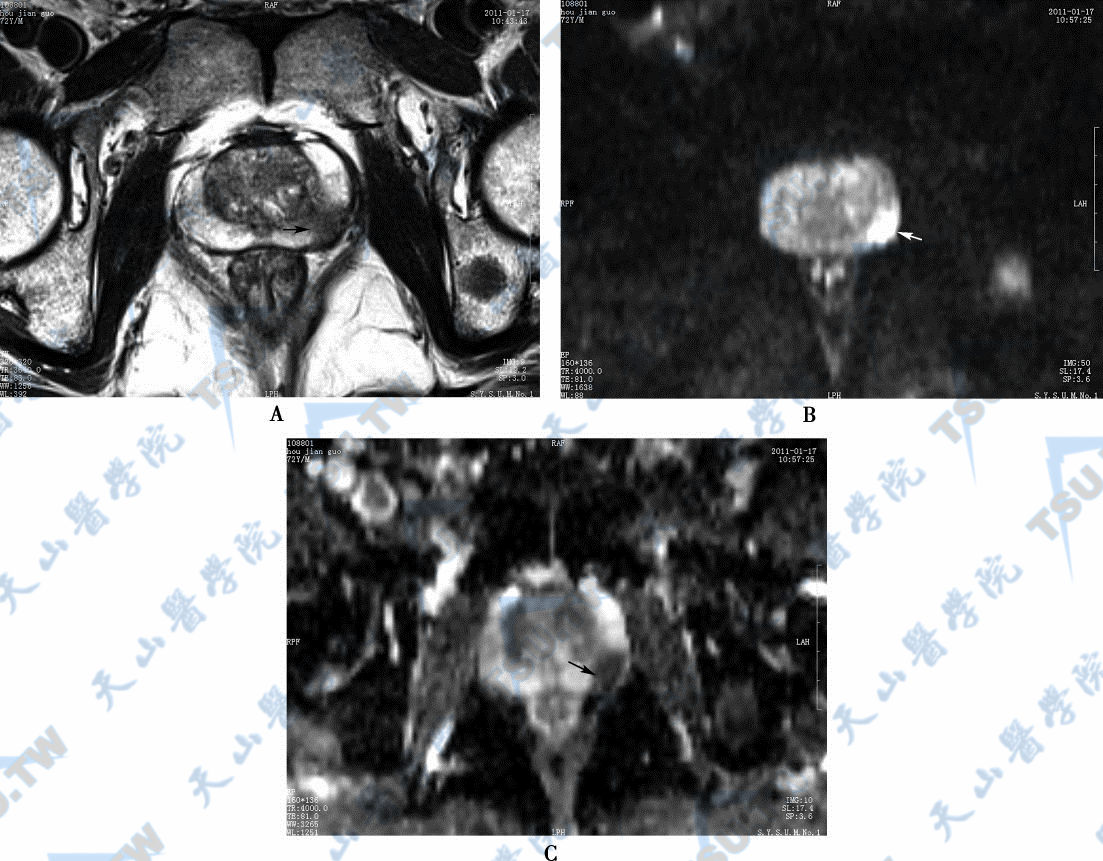

11大部分(约70%~75%)前列腺癌发生在外周带,少数前列腺癌(25%~30%)发生在内腺,可单发也可呈多中心发病,可边缘清楚,也可边缘模糊。MR T1WI示前列腺癌呈等信号,T2WI呈低信号(与正常前列腺外

12由于前列腺增生发生于移行区和尿道周围腺区,MR T2WI加权像上表现为前列腺体积增大,信号不均匀,外周带受压变薄,呈均匀高信号。前列腺增生结节包括以腺体增生为主的增生结节和以

13前列腺脓肿不太常见,临床上患者可能出现发热、会阴部胀痛不适。小的脓肿CT不易显示,脓肿增大时,CT可以显示,但总体上CT对脓肿提供的信息远少于MR。CT:表现为前列腺增大,其内可见不

15前列腺炎时前列腺体积可增大也可无增大,MR T1WI表现为片状等或稍低信号,T2WI表现为外周带多发低信号影(与正常前列腺外周带信号比较呈低信号),增强扫描病灶强化程度高于正常外周